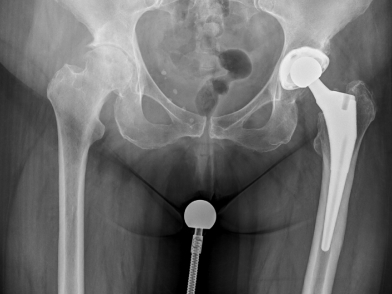

Η ριζική θεραπεία της οστεοαρθρίτιδας του ισχίου είναι η ολική αρθροπλαστική του ισχίου, δηλαδή η αντικατάσταση της άρθρωσης από τεχνητή.